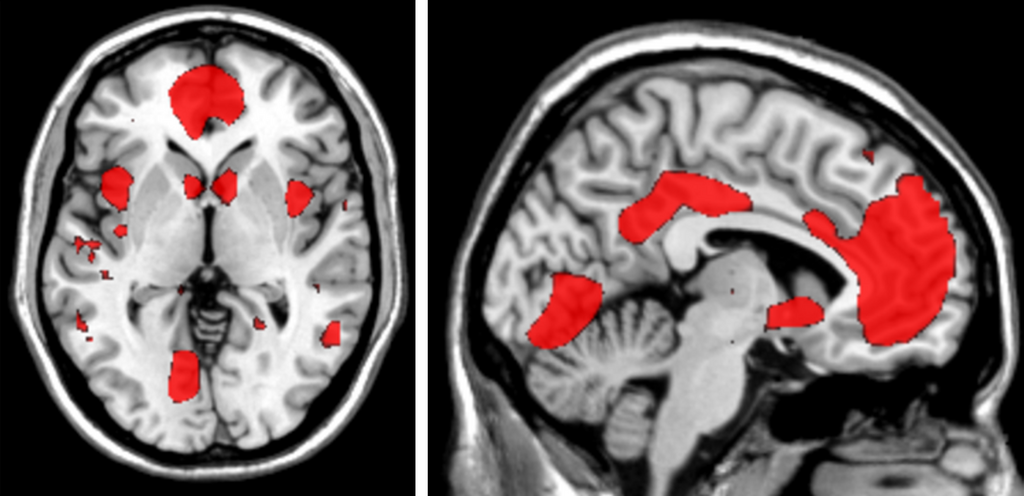

We set up the MRI to optimize our ability to measure whats happening in the hippocampus, an area of the brain thats critical for memory, says Trelle, the studys lead postdoc. We can actually see very distinct neural signatures when people successfully remember versus when they forget.

<strong>MEMORY IS REALLY</strong> complicated: This fMRI data from the Stanford Memory Lab shows the numerous areas of the brain (from two different angles!) that are recruited during successful memory retrieval.

The memory tests are sensitive enough to pick up subtle changes in recallsome of which are due to the gradual dulling of memory with age. Others may indicate something more serious, like the protein--buildup calling cards of Alzheimers. By watching memory lapses in action and comparing peoples performance over time, Trelle and her colleagues hope they can identify the early signs of memory decline and uncover its causes, as well as clues about how to prevent it.